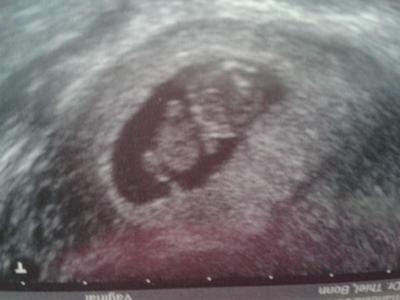

Hallo ihr lieben Ich bin so erleichtert. Heut hatte ich meinen nächsten fa termin und es war wunderbar:))) unser Gummibärchen ist so fit und ganz genau auf dentag entwickelt. Heut bin ich 9+0 und der wurm kst 2, 55 cm groß. War nur etwas verwundert weil mein eisenwert gar nicht bestimmt wurde? Kennt ihr euch aus? Mein alter Arzt hat den immer gemessen. Hab auch meinen neuen mutterpass bekommen. Häng euch noch ein Bildchen dran. Lg

Bild zu 10. ssw und fa Termin - Forum für März - Mamis